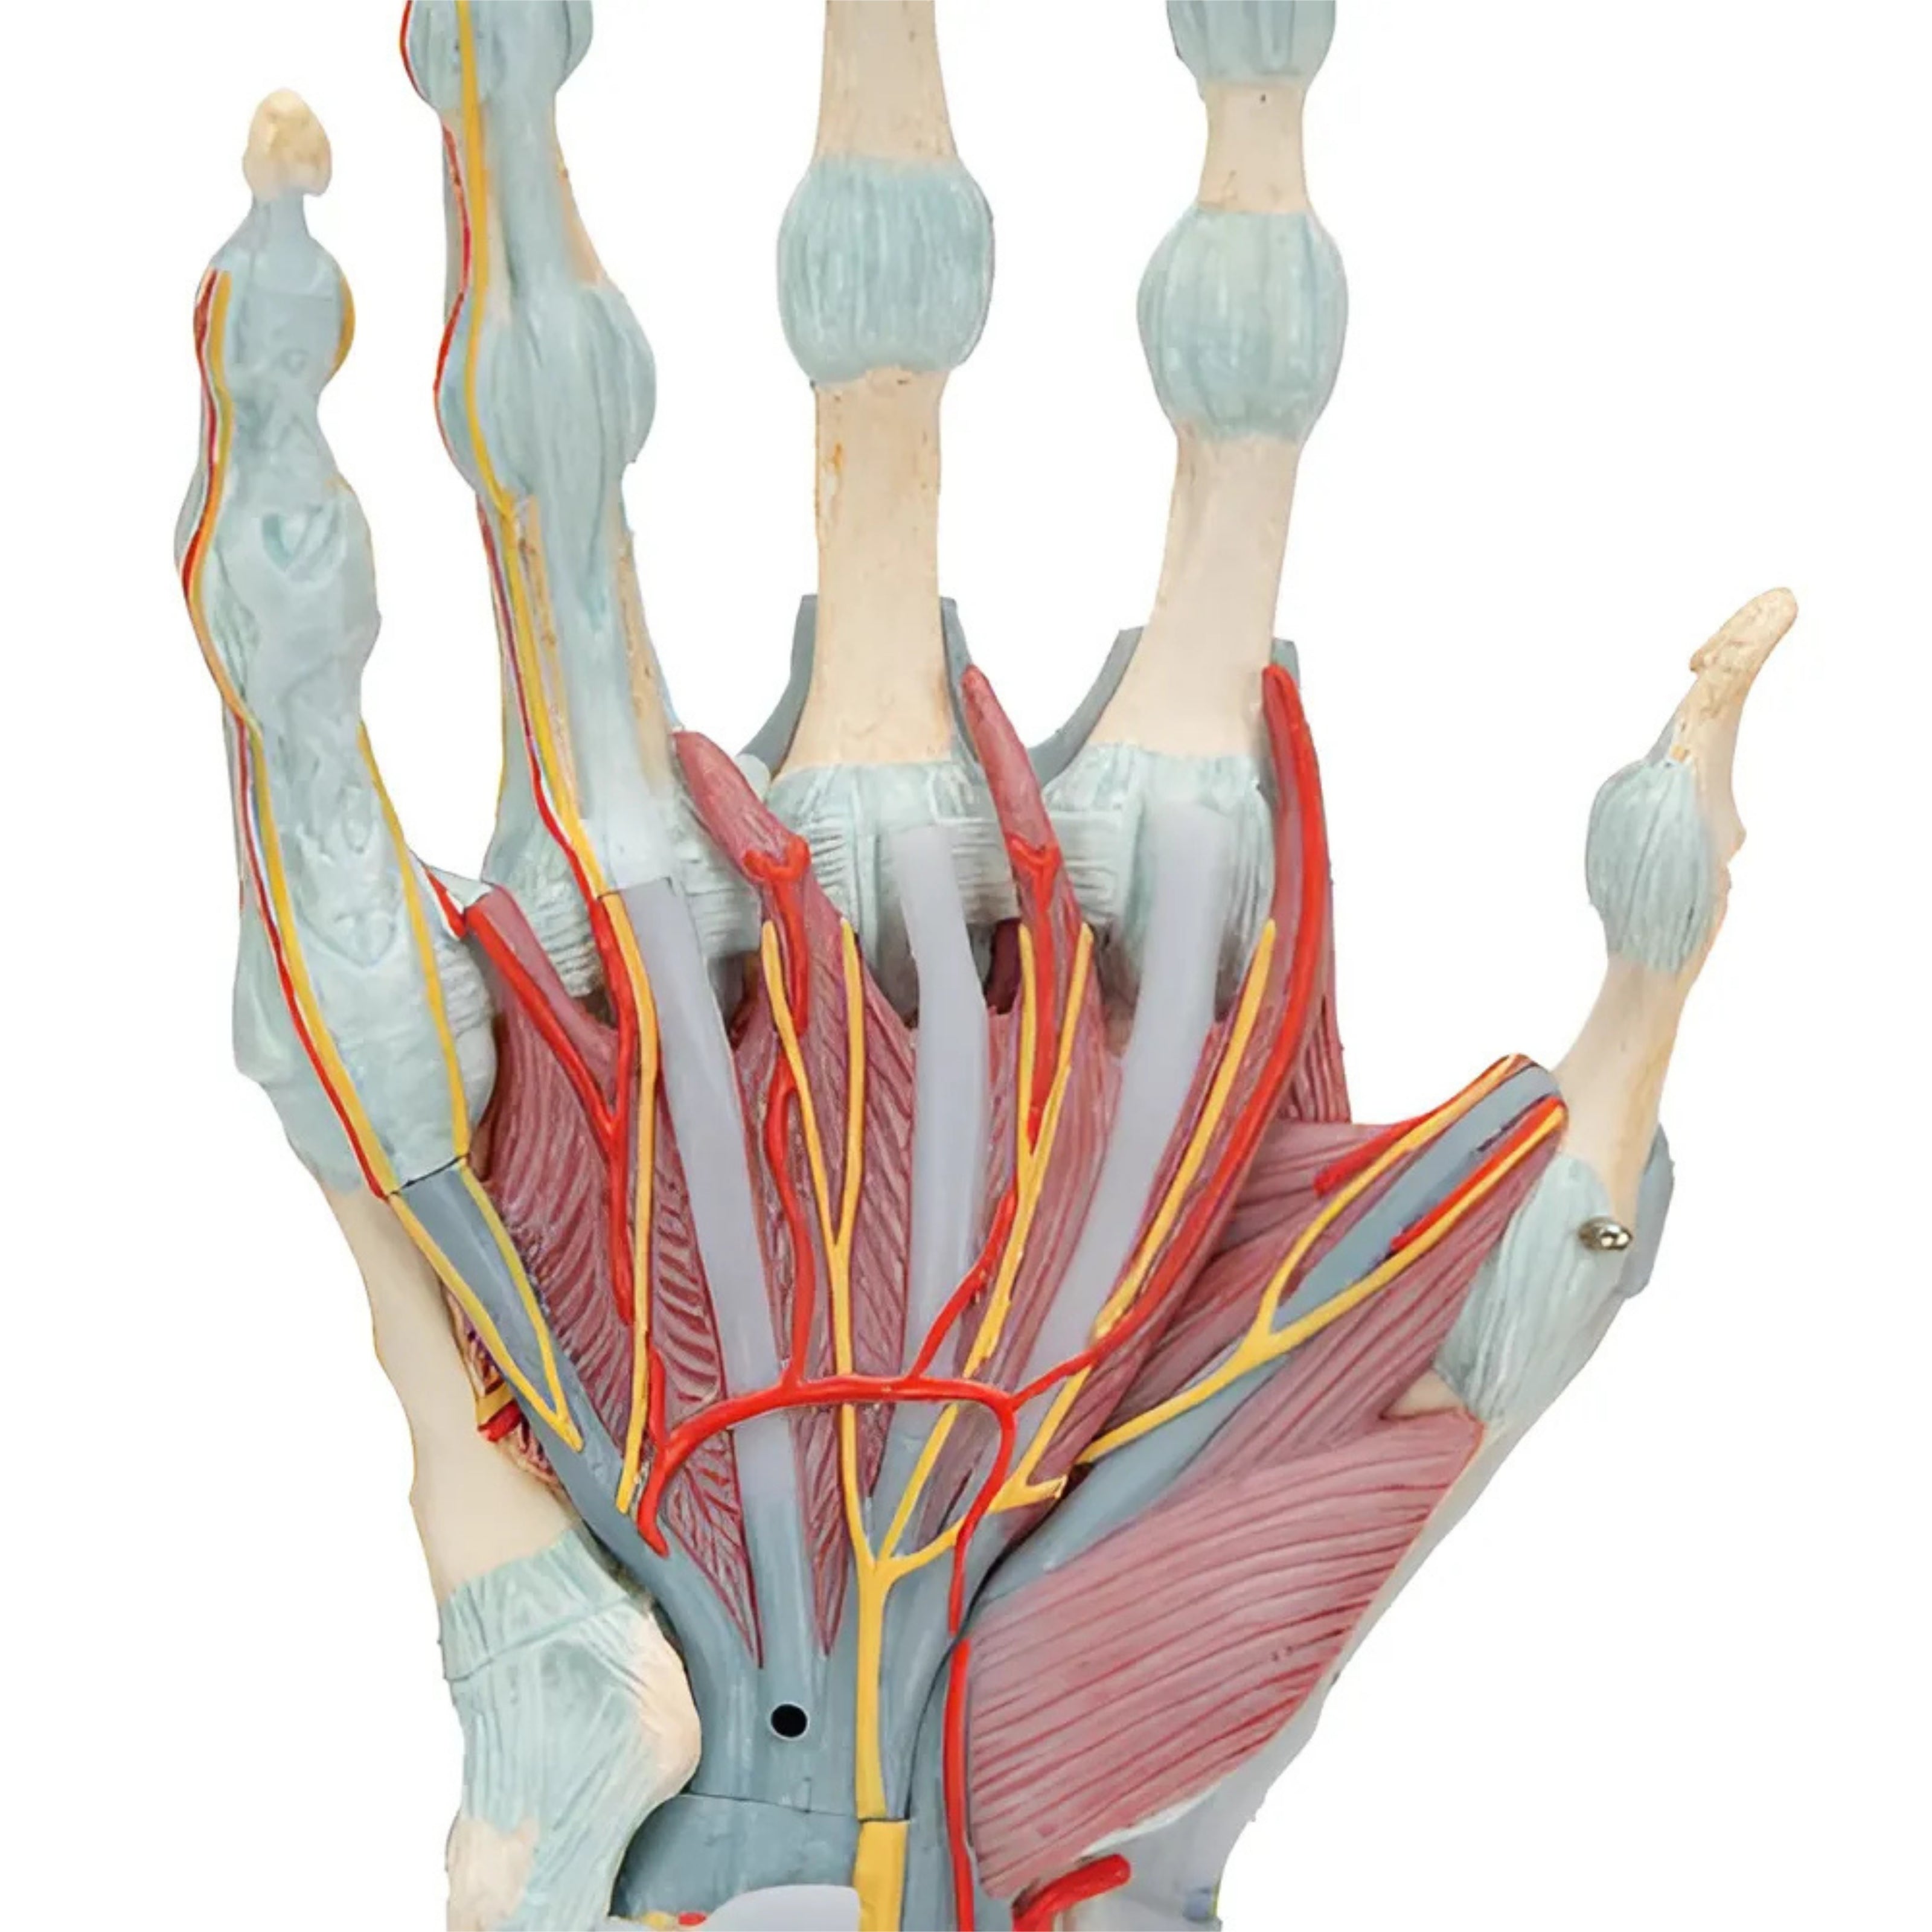

Modelo del esqueleto de la mano con ligamentos y músculos - 3B Smart Anatomy

Precio de venta$15,552.61